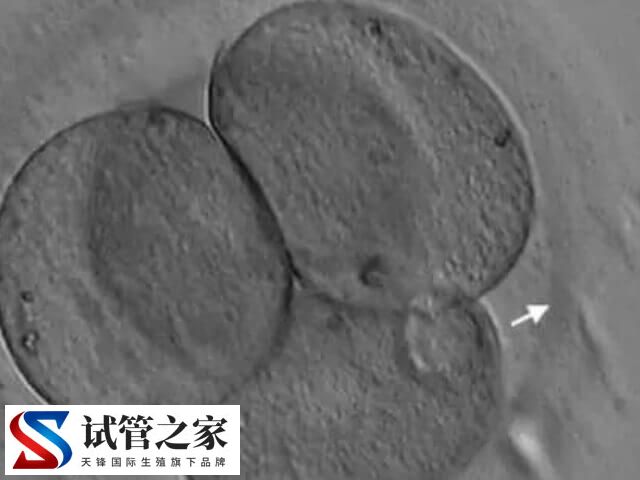

也就是说,通过化学、机械、或激光的方法对透明带进行打薄、打孔甚至完整切除,以帮助胚胎从透明带内孵化出来的技术,而这就是辅助孵化技术,旨在提高辅助生殖的成功率。

胚胎发育到囊胚阶段时,需突破透明带才能着床。若透明带过厚、过硬或形态异常,可能阻碍胚胎自然孵化。辅助孵化(人体胚胎孵化项目)相当于为胚胎“开窗”,使其更易与子宫内膜接触,增加着床机会。至于这适合哪些人,如下所示: